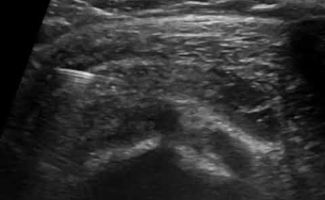

Η καθοδήγηση του υπερήχου εγγυάται τη σωστή και ασφαλή τοποθέτηση του κορτικοστεροειδούς εντός του θυλάκου, αποφεύγοντας την πιθανή έγχυση στον τένοντα, η οποία μπορεί να προκαλέσει φθορά του.

Σε συνδυασμό με την αντιφλεγμονώδη δράση του κορτικοστεροειδούς, η υπερηχογραφική καθοδήγηση παρέχει τη δυνατότητα υδροδιάτασης του θυλάκου πριν την έγχυση του κορτικοστεροειδούς. Η υδροδιάταση περιλαμβάνει έγχυση φυσιολογικού ορού και τοπικού αναισθητικού προκειμένου να εξουδετερωθούν οι συμφύσεις εντός του θυλάκου.